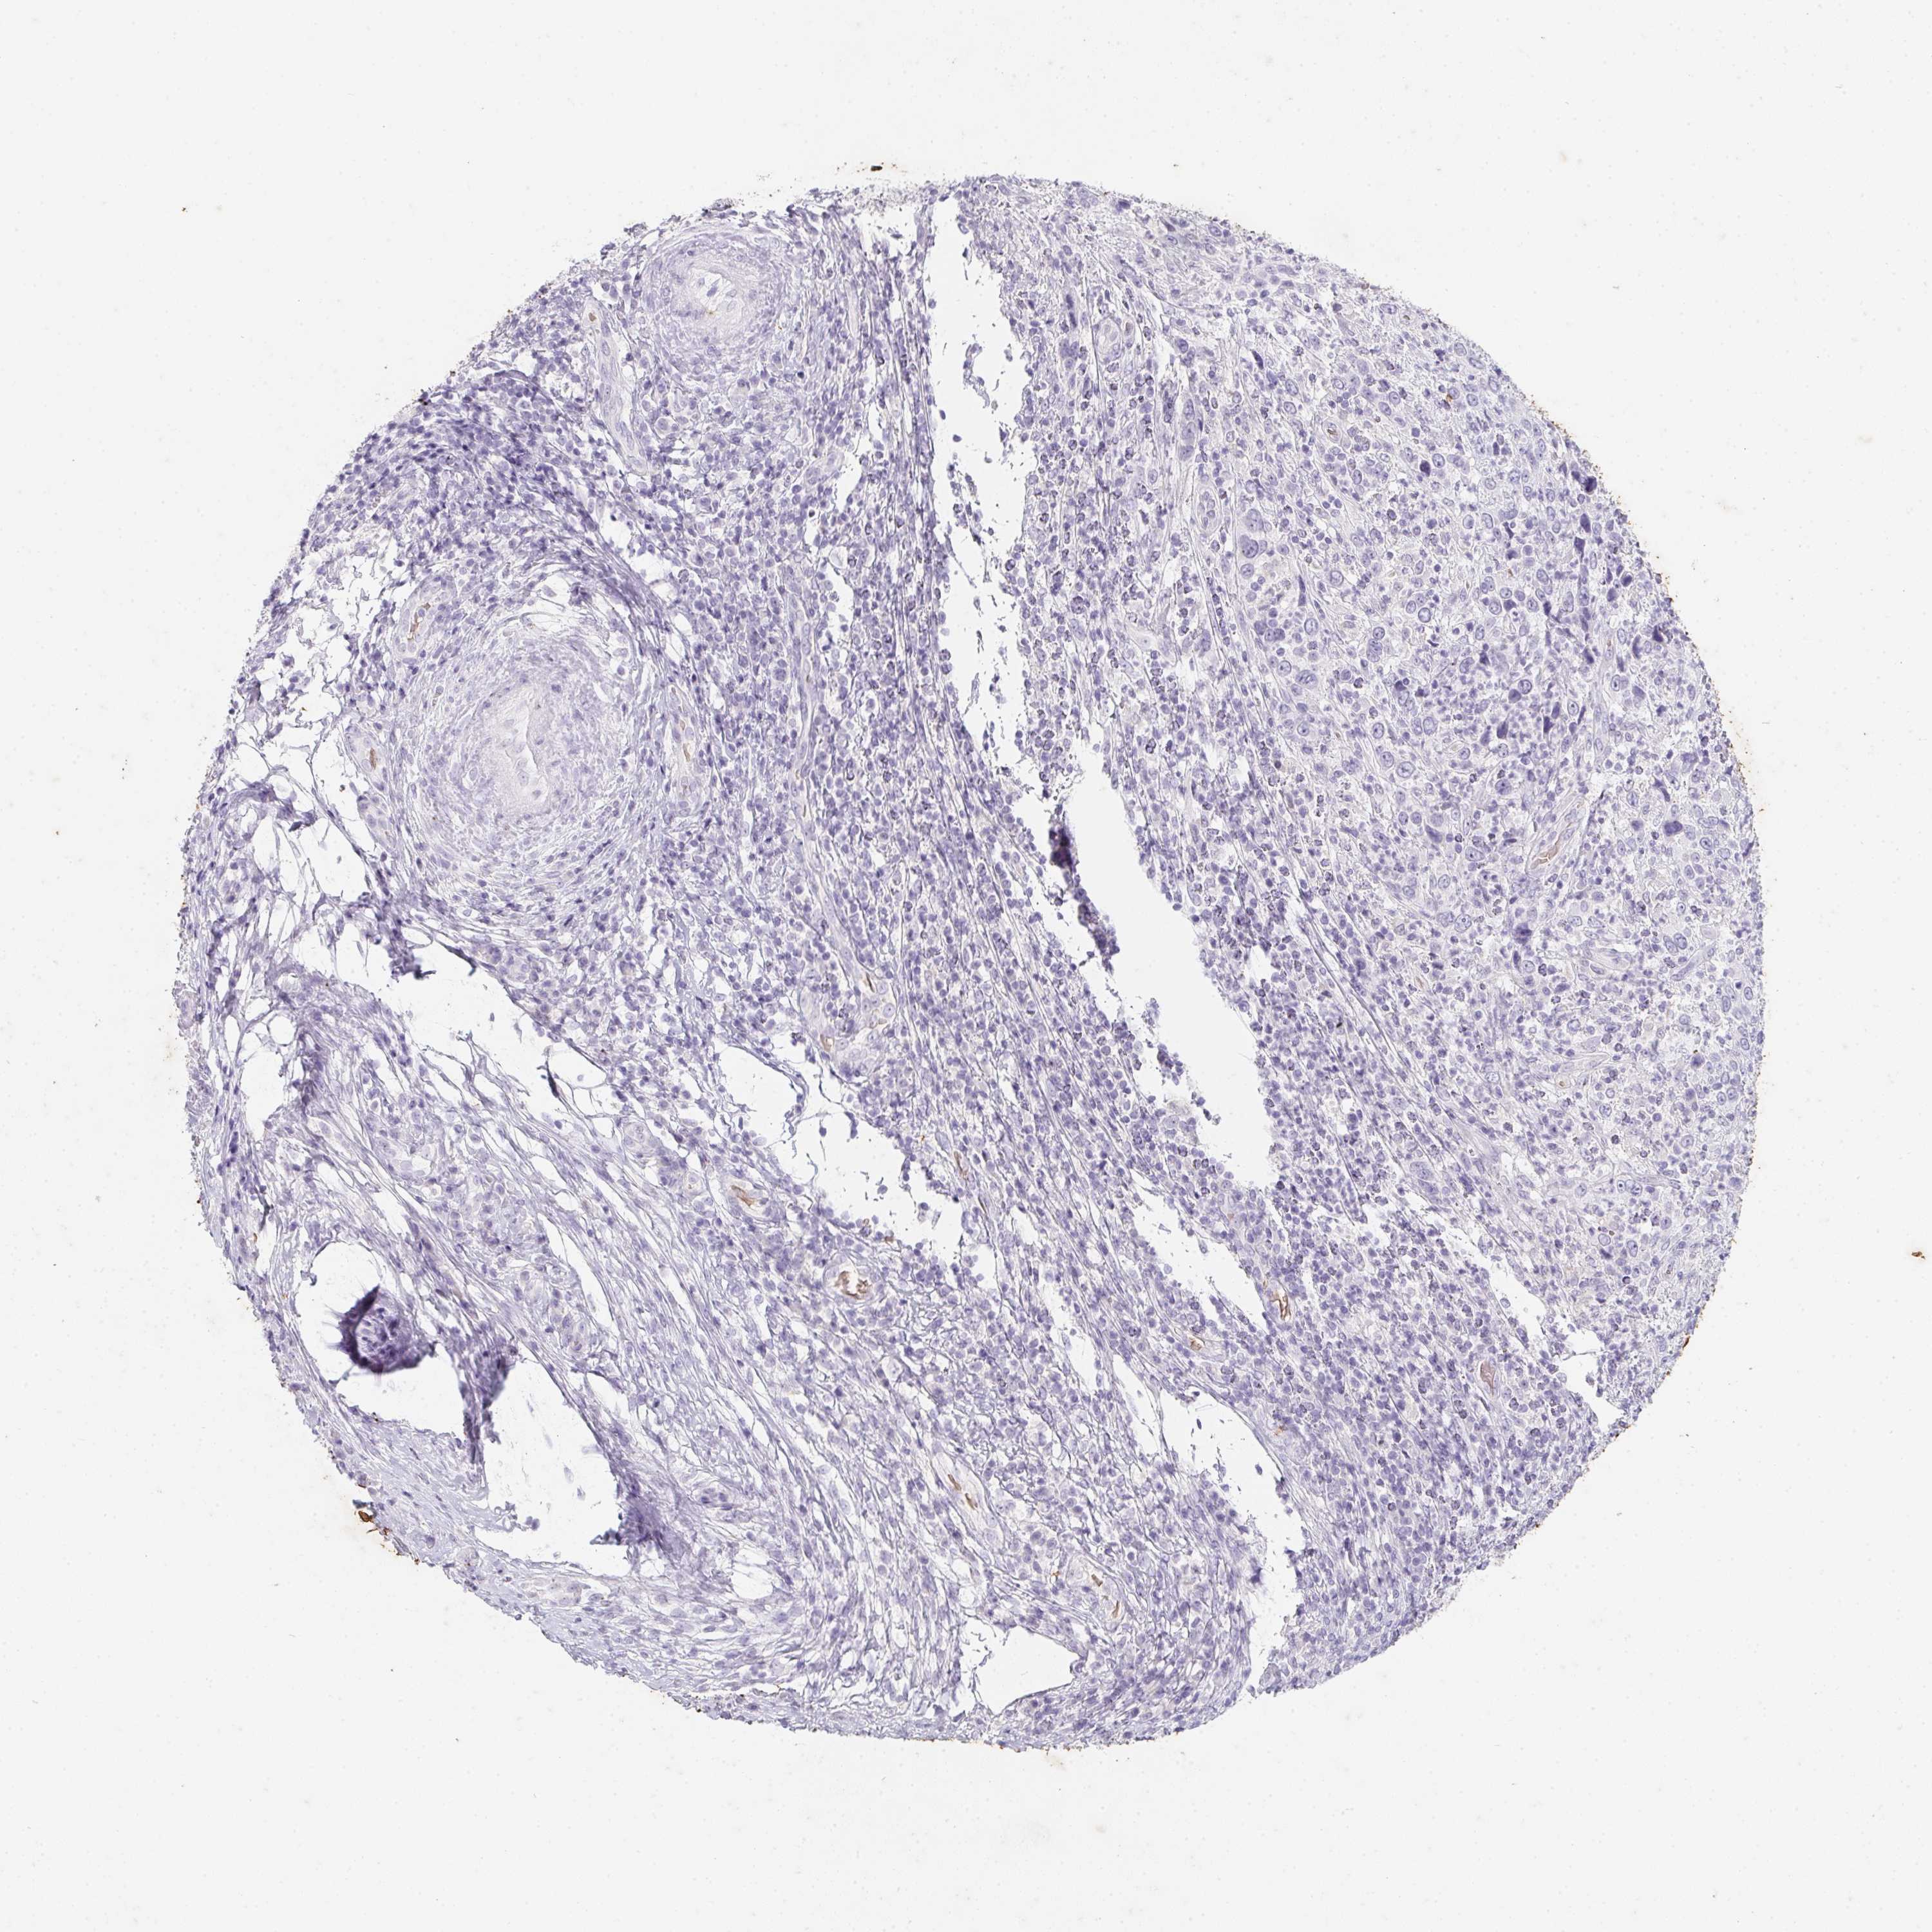

CERVICAL CANCER - Protein expressioni

A mouse-over function shows sample information and annotation data. Click on an image to view it in a full screen mode. Samples can be filtered based on level of antibody staining by selecting one or several of the following categories: high, medium, low and not detected. The assay and annotation is described here.

Note that samples used for immunohistochemistry by the Human Protein Atlas do not correspond to samples in the TCGA dataset.

Antibody stainingi

Antibody staining in the annotated cell types in the current human tissue is reported as not detected, low, medium, or high, based on conventional immunohistochemistry profiling in selected tissues. This score is based on the combination of the staining intensity and fraction of stained cells.

Each image is clickable and will lead to virtual microscopy that enables deeper exploration of all samples and also displays staining intensity scores, fraction scores and subcellular localization as well as patient and tissue information for each sample.

Antibody HPA063967

Staining

High

Medium

Low

Not detected

Intensity

Strong

Moderate

Weak

Negative

Quantity

>75%

75%-25%

<25%

None

Location

Nuclear

Cytoplasmic/membranous

Cytoplasmic/membranous,nuclear

Squamous cell carcinoma, NOS

Adenocarcinoma, NOS